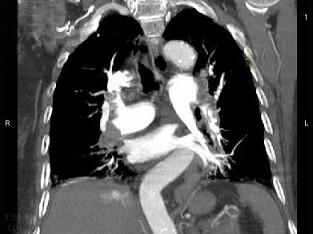

问题 82岁,女性,突发右侧胸痛,呼吸急促,行急诊CT检查,如图所示,请选择最佳答案 ( )

选项 A、肺动脉栓塞 B、肺动脉瘤 C、肺门淋巴结肿大 D、肺动静脉瘘 E、中央型肺癌

答案 A